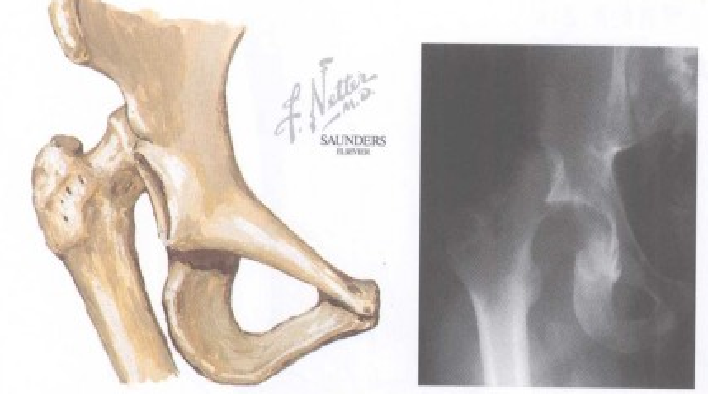

股骨头与脱臼位置关系和撞击力的方向决定所产生的损伤类型。以髂坐线(Nelaton)为标准:前方——前脱位后方——后脱位中心脱位:股骨头突破髋臼底部或入盆腔(合并有髋臼横行骨折,或髋臼顶骨折或者髋臼复杂性骨折,并入髋臼骨折处理)

Nelaton 氏线:坐骨结节至髂前上棘的连线。正常情况下,此线经过大转子尖端,当股骨颈骨折或髋关节后脱位时,大转子尖端可向上移位超过此线。